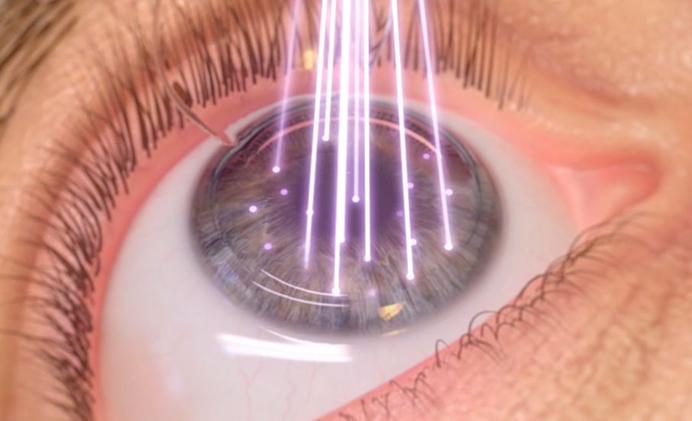

La cirugía refractiva constituye el avance tecnológico más impresionante de la medicina oftalmológica de los últimos años. La cirugía refractiva con láser, ya sea el LASIK o el PRK, actúa remodelando la superficie corneana, permitiendo neutralizar el vicio visual (miopía, hipermetropía o astigmatismo). Existen varios requisitos clínicos para postular a este seguro y eficaz procedimiento: